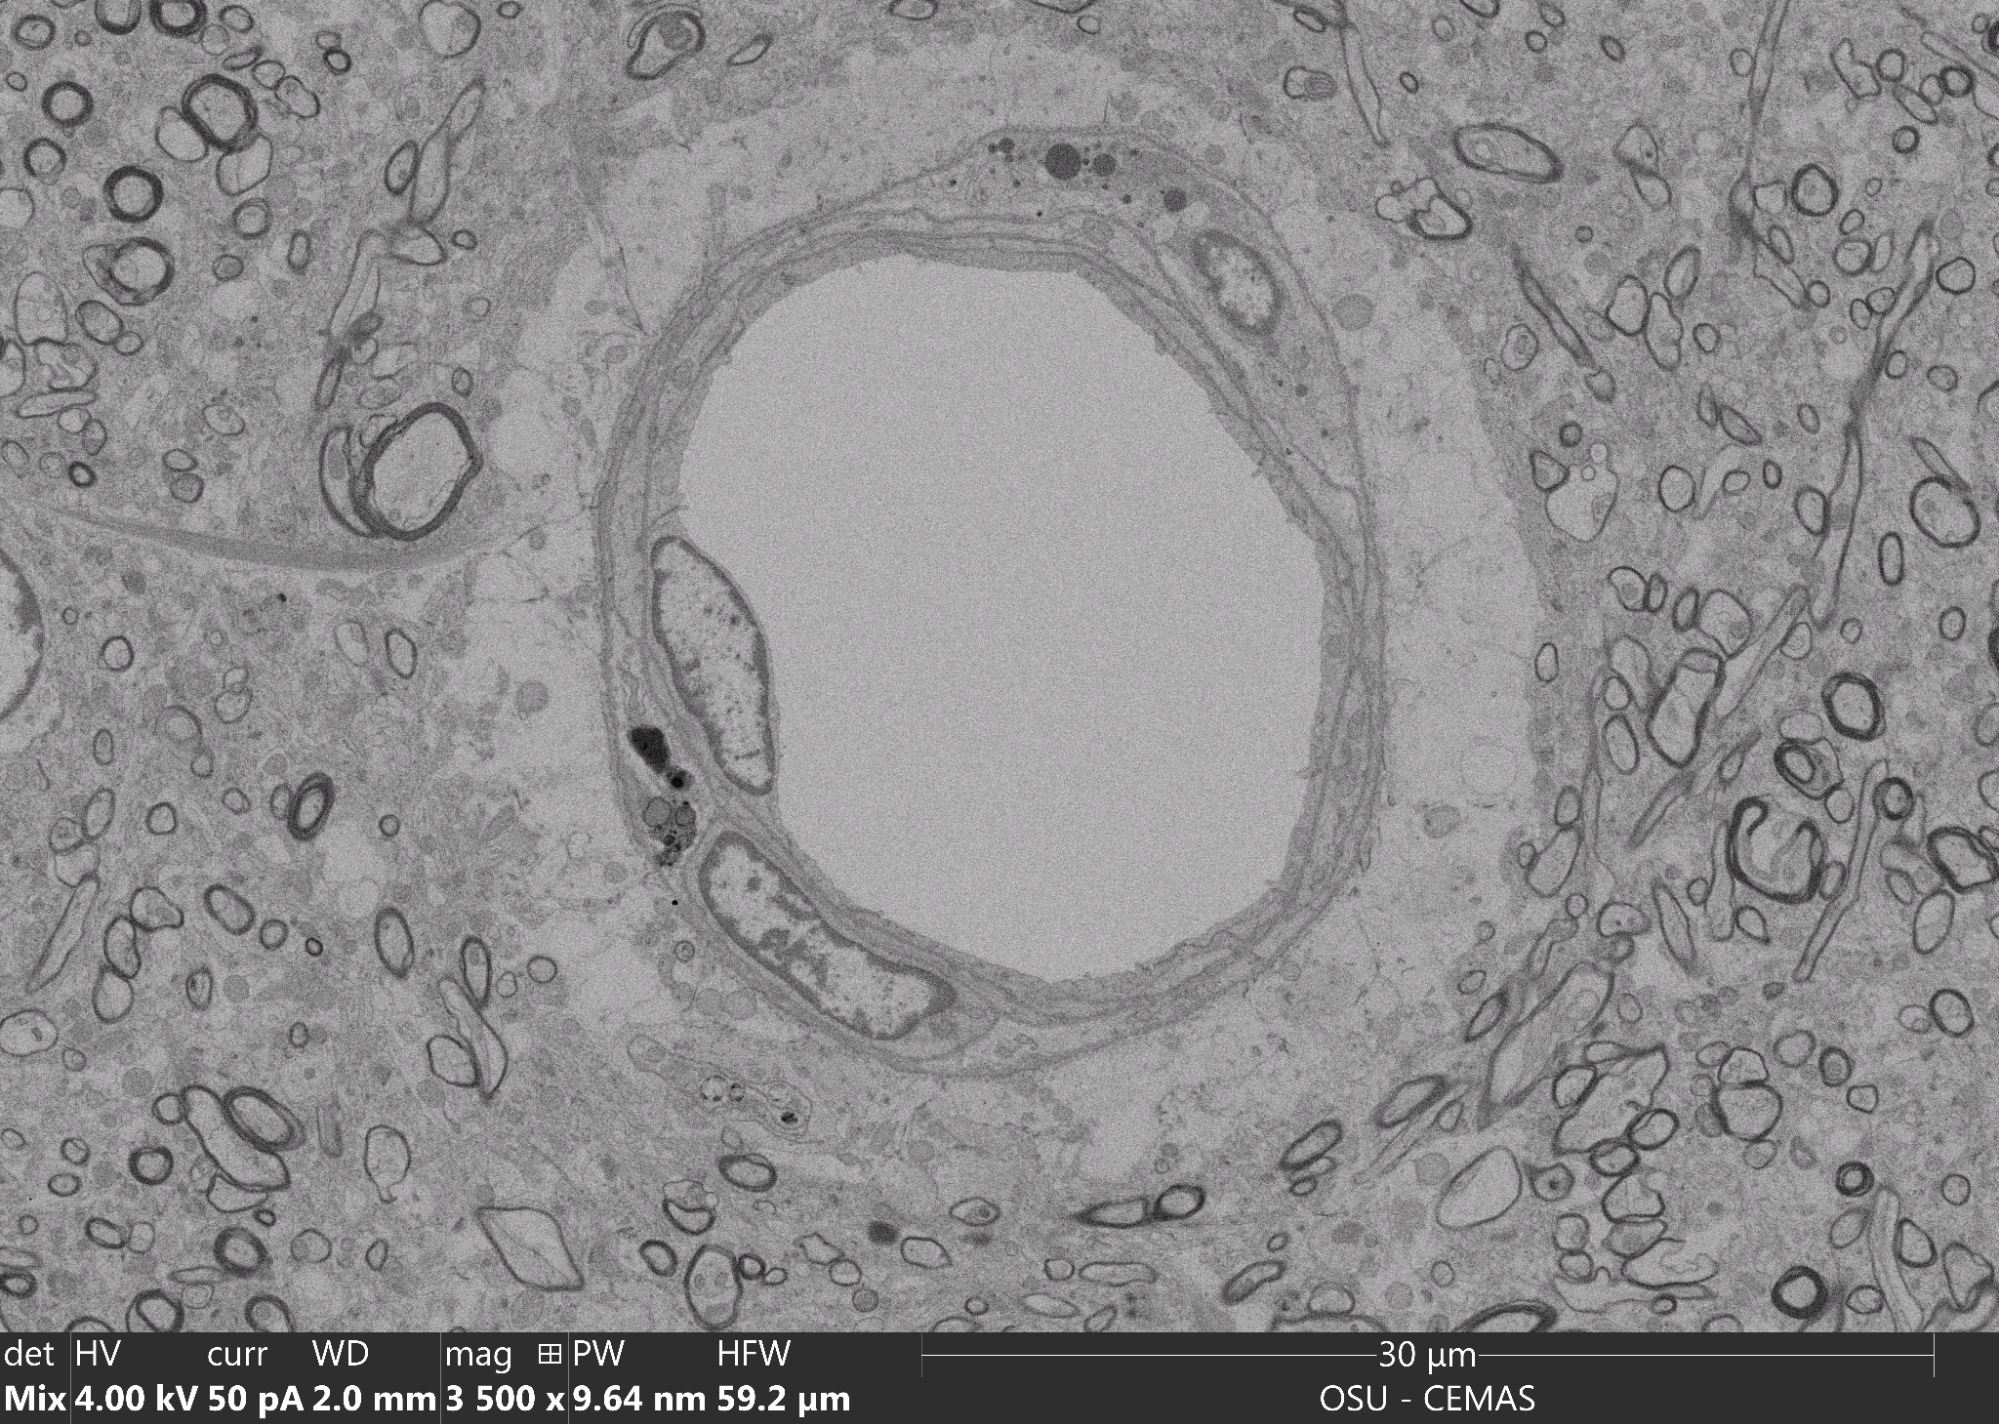

Electron micrograph from the best human preservation I’ve done to-date. ~90 minutes post-mortem time from a MAiD donation case. The large white space in the middle is a capillary. Here you can find substantial perivascular edema (the white area around the capillary), as well as neuropil that’s concerningly indistinct. I asked Ken Hayworth to review these images; he does not think they’re traceable. Additionally, some regions of this brain failed to perfuse entirely; this is from a well-perfused region.

It is the best-preserved whole human brain I’ve ever seen. It is also—like every other human brain I preserved with any appreciable post-mortem delay—not traceable. It’s not a quality I (or the BPF) can accept. Looking at the degree of damage scares me.

I originally thought that humans might have a two-hour post-mortem preservation window. If that had been true, I would have probably worked to integrate preservation into hospices across the country. After reviewing the electron micrographs from animals and humans under various preservation conditions, it became clear that the hospice model was nonviable. We couldn’t wait for a person to die on their own timeline and only then begin our procedure. We’d need them to undergo a full process involving Medical Aid in Dying (MAiD)—and before we could promise any benefits from such a process, we needed to perfect it on animals.